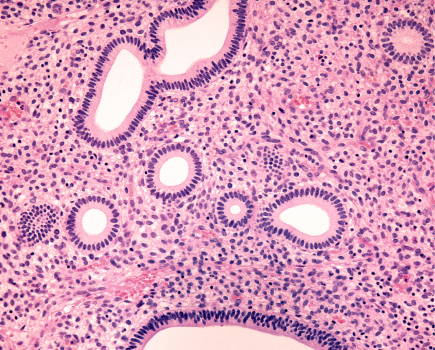

L’invasion lymphovasculaire (LVSI) est un facteur pronostique majeur du cancer de l’endomètre, désormais intégrée à la classification FIGO 2023 qui distingue la LVSI focale (< 5 vaisseaux) de la LVSI substantielle (≥ 5 vaisseaux), associée à un upstaging automatique en stade IIB.